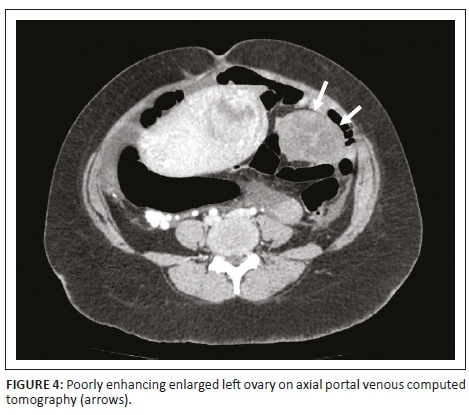

The decision was made to induce labour based on the unclassified proteinuria and the clinical suspicion of possible underlying pre-eclampsia. During the induction of labour, foetal monitoring showed subtle signs of foetal distress, which warranted continuous monitoring, but despite in-patient care and continuous foetal monitoring, there was subsequent intra-uterine foetal demise and the patient delivered a stillborn baby via NVD. Following delivery, the patient's condition deteriorated in the ward, developing a persistent unexplained tachycardia of approximately 150 bpm, a blood pressure of 156/119 mmHg and a serum calcium level well above normal limits (4.25 mmol/L, normal limit is 2.62 mmol/L). Emergent cross-sectional imaging in the form of contrasted CT abdomen showed a large cystic mass with a thick, irregular enhancing wall and septations (Figure 1), which was inseparable from the uterine fundus (Figure 2). In addition, extensive left ovarian and pelvic vein thrombosis (Figure 3) and an enlarged, poorly enhancing left ovary were noted (Figure 4).